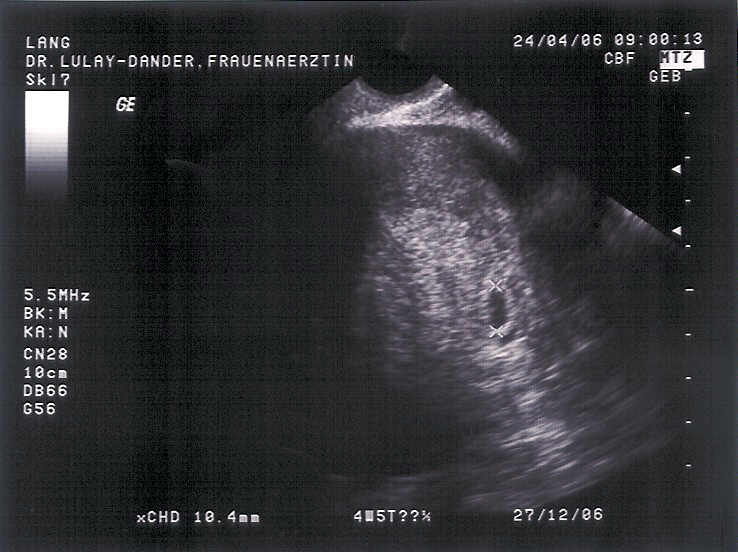

Anbei das erste Bild von meinem Krümel! Das schwarze Böhnchen rechts im Bild.

Dateianhänge

1. US 240406.jpg.jpg

Gesehen hat man eine Fruchthöhle und eine Zyste, vielleicht wird aus der Zyste ja auch noch ein 2. Kind. Also nach Meinung der Ärztin ist die sich nicht sicher, ob es eben eine Zyste oder eine 2. Fruchthöhle ist (bei ihr kam es schon öfter vor, dass eine Zyste dann ein Kind war - sagte sie noch blöd grinsend). *mecker*

Ich muss in 2 Wochen nochmal hin zum Ultraschall. Auch kommt mir ihre Errechnung des Geburtstermins komisch vor. Sie hält sich an die Größe von dem einen vom heutigen Ultraschall und da bin ich heute in der 6. Schwangerschaftswoche, Entbindungstermin ist der 25.12. und letzter Arbeitstag der 12.11.06 - so steht es auch auf der Bescheinigung für den Arbeitgeber.